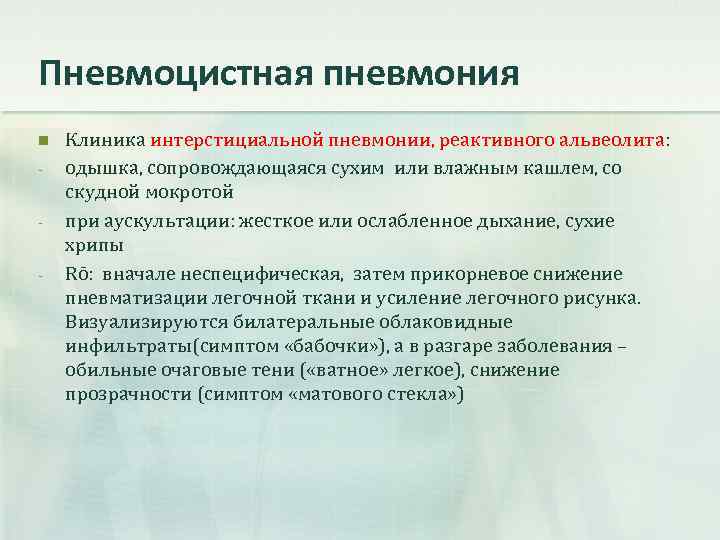

Рентгеновские снимки при пневмоцистной пневмонии